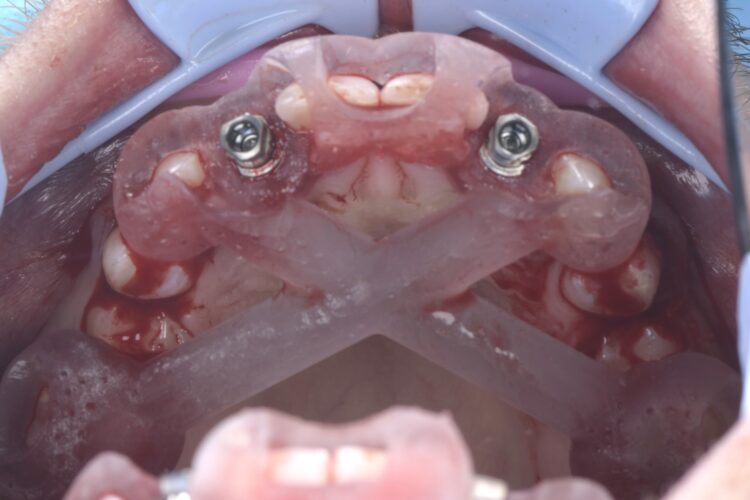

A CBCT scan was taken using a Morita X800. This dataset was imported into the planning software, where it was merged with the STLs of the anatomically correct diagnostic digital wax-up and modules.  With the anatomically correct diagnostic wax-up, there was no ambiguity regarding planning the implant position, angle and depth with precision. I like to plan these types of cases myself, but it is possible to outsource the planning stage for clinicians who are new to the process and looking to increase their workflow efficiency. For this case, I wanted to build up the gingival thickness in order to improve the papillae around the implant sites. The surgical plan, therefore, included soft tissue grafting.

On the day of surgery, a split-thickness envelope flap was raised. Two CONELOG® Progressive-Line implants were placed through the surgical guide in the pre-determined lateral incisor positions. Soft tissue augmentation was performed simultaneously with the implant placement, and the site was sutured and closed without tension. The implants were immediately loaded using provisional crowns that were pre-fabricated in the lab.

This case presentation shows a real-life result of the kind of treatment we deliver every day in our clinic. It also demonstrates how a guided workflow allows us to place implants exactly as planned, making the process easier and more efficient.